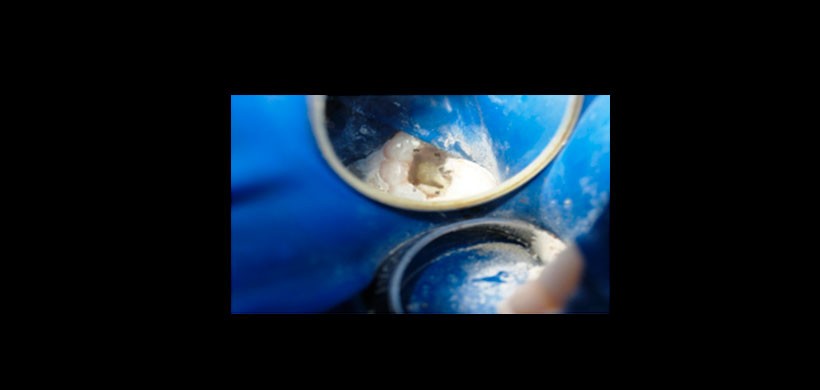

Figura 3: Visualización de la entrada de los conductos radiculares.